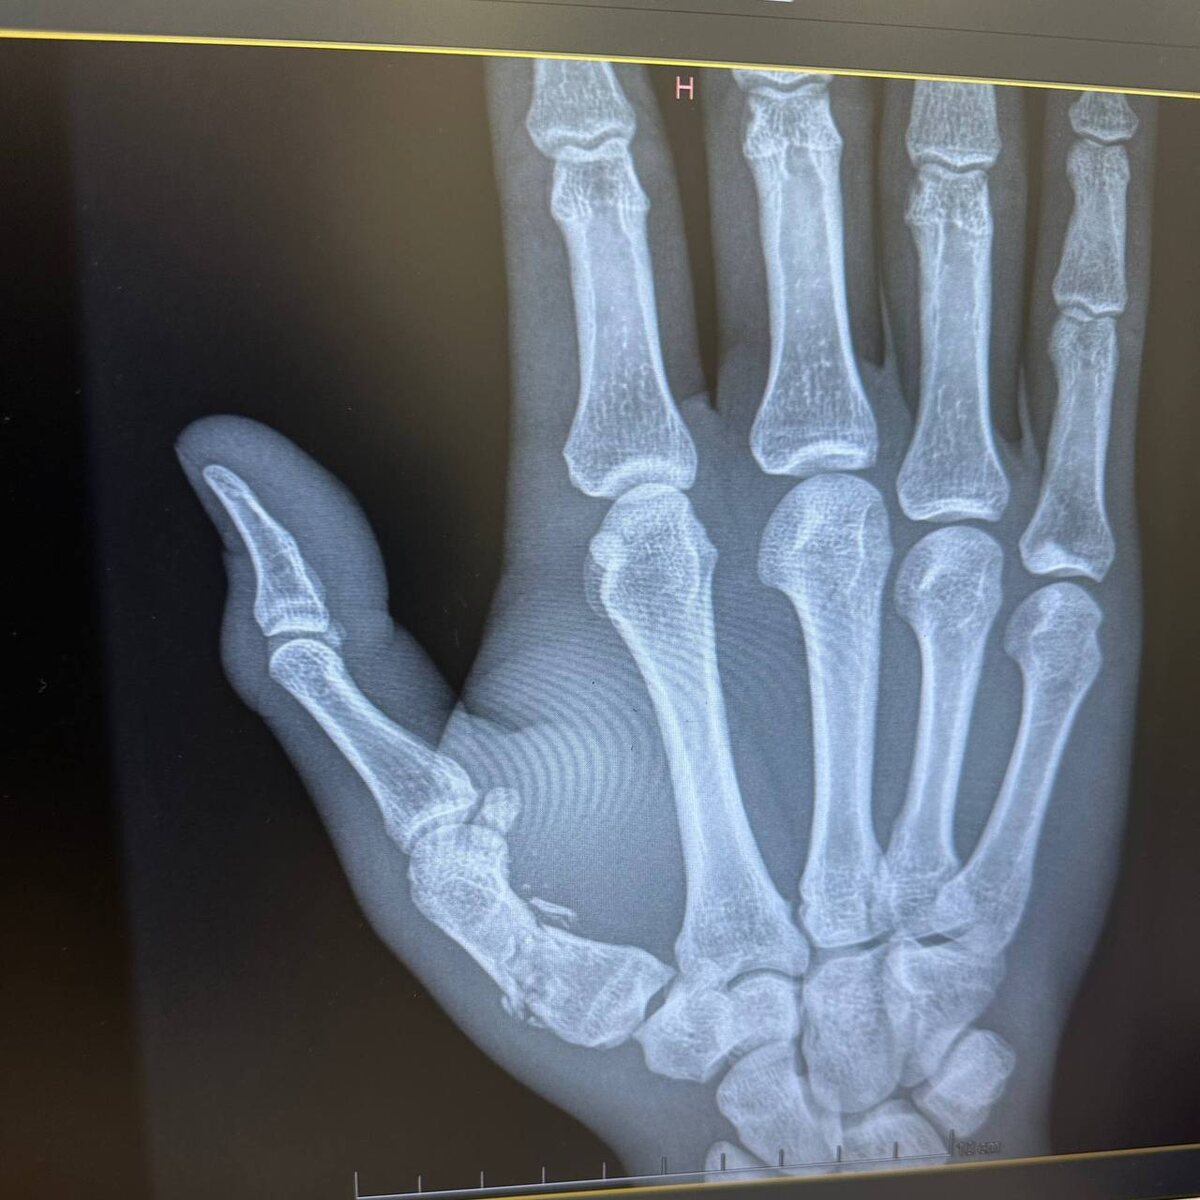

❌Мало того, что Андрей уступил решением на UFC 324, так еще и выяснилось, что в бою с камерунцем он сломал руку. Здоровья нашему бойцу! 👍Поддержи наш канал cвоим голосом 📺Смотрим бои в прямом эфире ⚡ @teleudar

❌Мало того, что Андрей уступил решением на UFC 324, так еще и выяснилось, что в бою с камерунцем он сломал руку. Здоровья нашему бойцу!